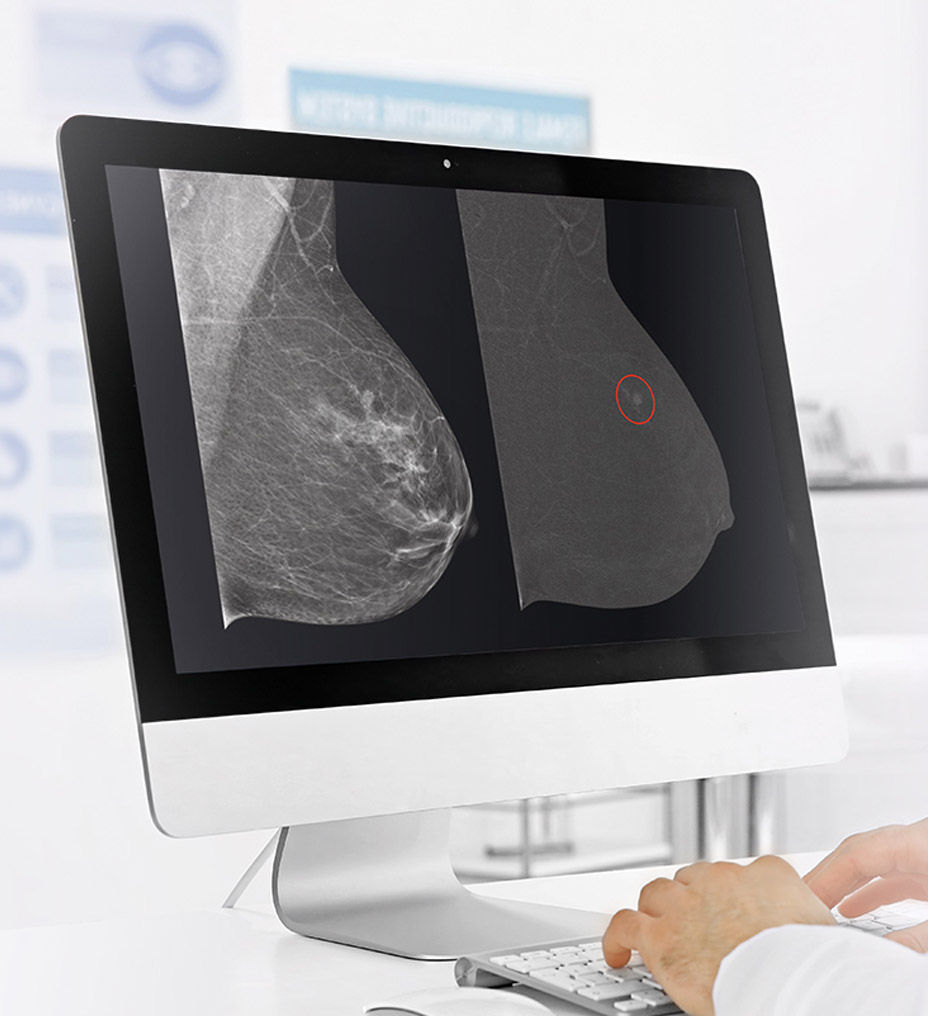

See differently, see in contrast

SenoBright™ HD

Contrast-Enhanced Mammography advanced application

Reduces the masking effect of breast tissue to reveal what matters1.